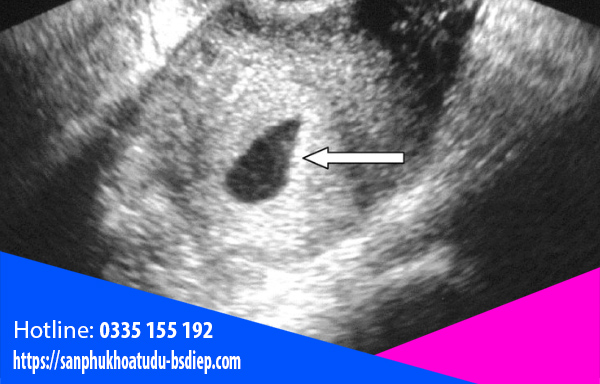

Nhiều người thắc mắc thai ngoài tử cung siêu âm có thấy không? Đây là điều dễ hiểu, bởi mang thai ngoài tử cung không giống bình thường. Tuy nhiên, câu trả lời là “Có” nhé. Sẽ có những cách sau để xác định tình trạng mang thai:

Siêu âm đầu dò

Thông thường, khi mẹ bầu bị trễ kinh lâu ngày và có hiện tượng mang thai thì đi khám. Bác sĩ khi siêu âm tử cung không thấy thai làm tổ sẽ chỉ định siêu âm ổ bụng để xem thai làm tổ ở đâu. Nếu không thấy thì sẽ tiến hành siêu âm đầu dò bằng cách dùng một dụng cụ đưa vào cổ tử cung. Đầu dò sẽ cho hình ảnh chính xác và độ nhạy cao. Siêu âm được các bộ phận buồng trứng, vòi tử cung, ống dẫn trứng… Như vậy sẽ dễ dàng tìm thấy và xác định được vị trí làm tổ của phôi thai.

Siêu âm đầu dò cũng giúp bác sĩ chẩn đoán được cả tình trạng chảy máu ổ bụng và các hiện tượng liên quan khác.

Tuy nhiên, kỹ thuật này yêu cầu khá phức tạp, đòi hỏi người bác sĩ phải có trình độ chuyên môn cao và am hiểu, biết cách sử dụng thiết bị hợp lý.